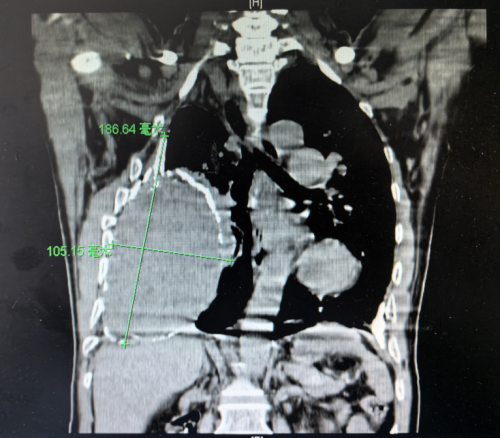

(南华大学附属长沙中心医院)胸外科、心脏大血管外科,科室主任、主任医师袁跃西查看了张根水的胸部CT,清晰可见他的右侧胸腔存在一个巨大的慢性包裹性脓胸,因为病程长,病灶迁延不愈,包裹的纤维板已经钙化为一层厚厚的硬壳,脓腔里还有18×10cm机化的坏死组织,宛如一个“硬壳鸵鸟蛋”塞进了他的胸腔。

术前CT

袁跃西告诉患者及家属,根据CT显示,包裹性脓胸已经严重压迫到患者的右肺组织,阻碍了肺的扩张,使肺功能受到限制,所以患者一活动就喘不上气。“这是由结核杆菌感染后未规范治疗、迁延不愈造成的慢性脓胸。”袁跃西介绍,患者三十年前确诊结核性胸膜炎,吃了6个月的抗结核药后症状消失,就没有再复查和规范治疗,“当时症状是没有了,但结核病灶并没有完全被‘杀死’,导致结核性胸膜炎迁延不愈,形成包裹性脓胸。”如果持续发展,随着脓腔里的坏死机化组织不断累积,脓腔会越来越大,右肺可能因受压萎缩失去功能,还可能造成纵膈左移压迫对侧脏器,使患者呼吸衰竭,甚至出现更多并发症而危及生命。